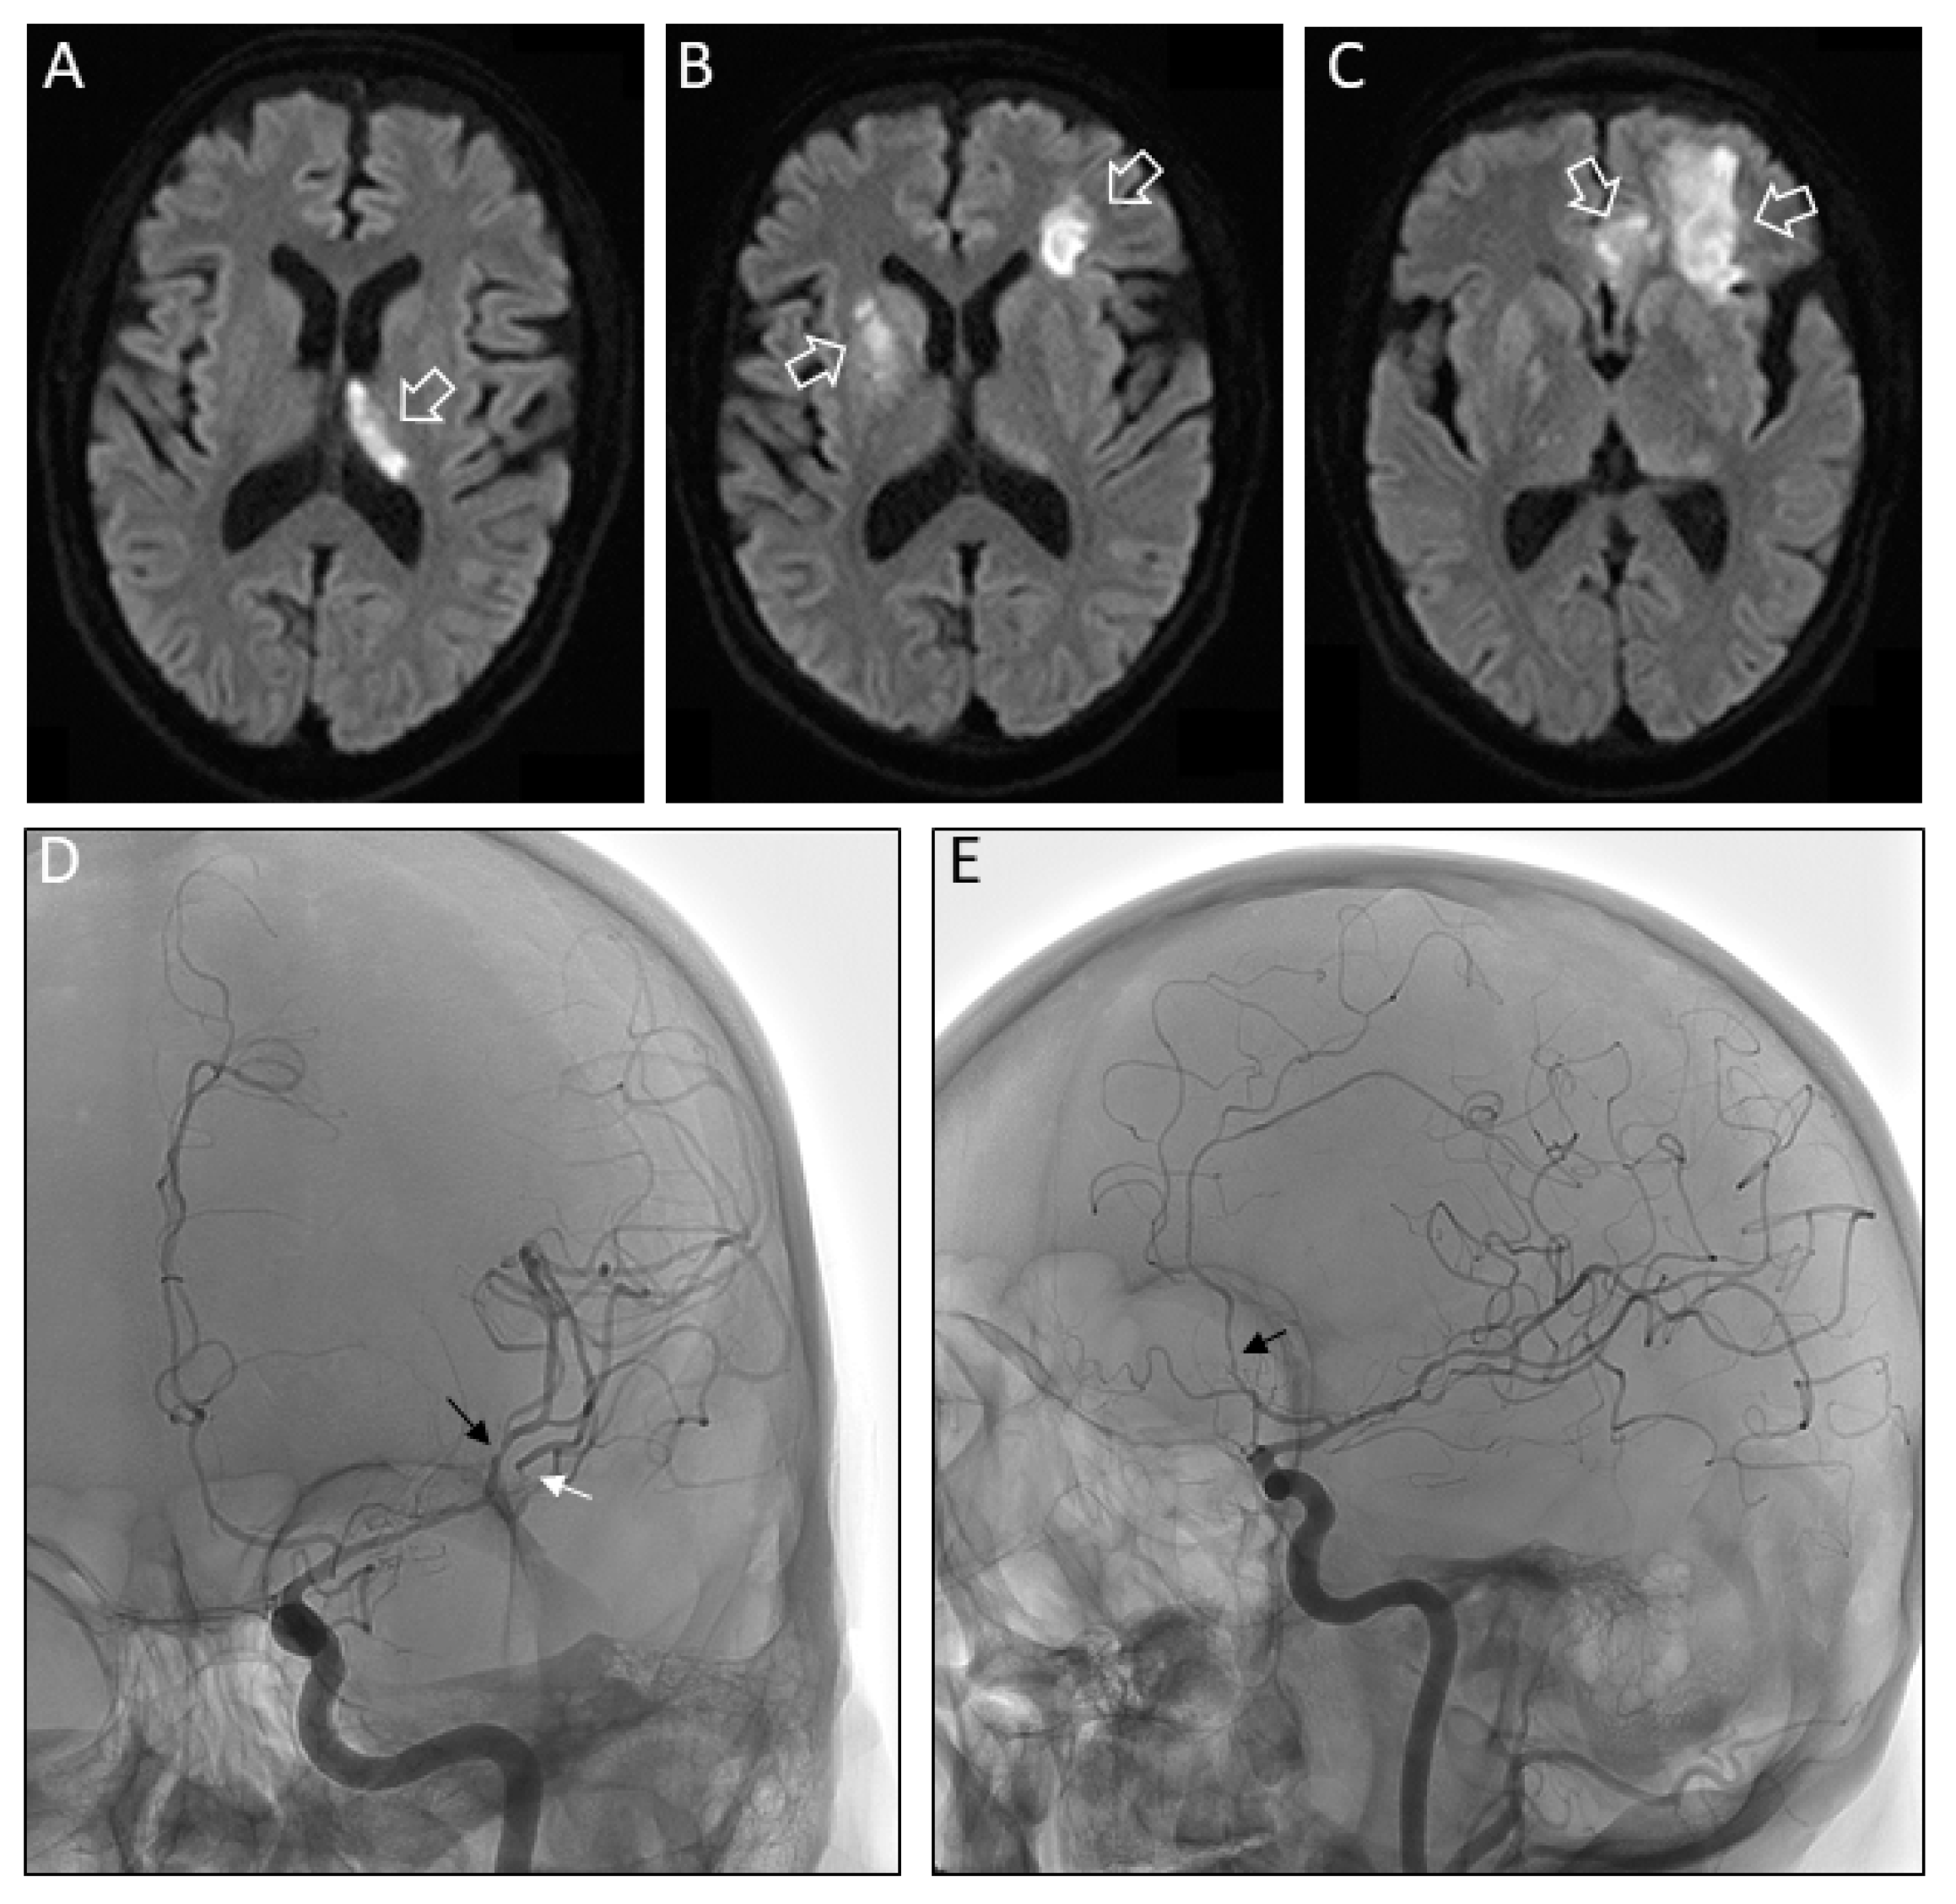

Cerebral HSV-1 Vasculitis as a Fatal Complication of Immunosuppression in Non-Hodgkin´s Lymphoma: A Case Report and Review of the Literature

2. Case Study